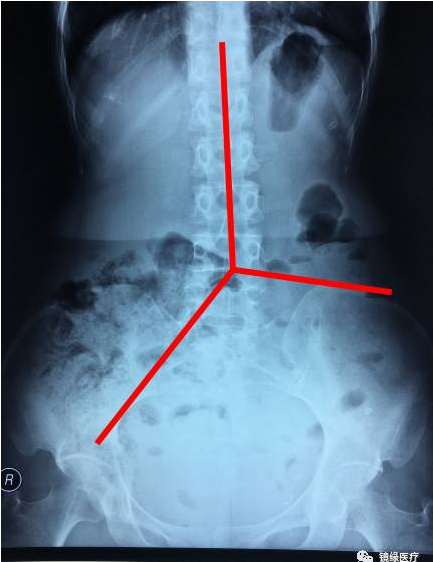

首先, 根据骨性标志把X光片分为三个区域:

从胸椎棘突至第五腰椎棘突作连线;自第五腰椎棘突向右侧骨盆出口和左侧

髂骨作切线,分为三个区段:

R=右半结肠区

L=左半结肠区

RS=直肠乙状结肠区

如下图所示:

然后我们根据每个区域剩余标记物的数量计算传输指数(TI): TI=RS/(RS+R+L);

0≤TI<0.5,慢传输型便秘;

0.5<TI≤1,排便障碍型便秘;

TI=0.5,混合型便秘。